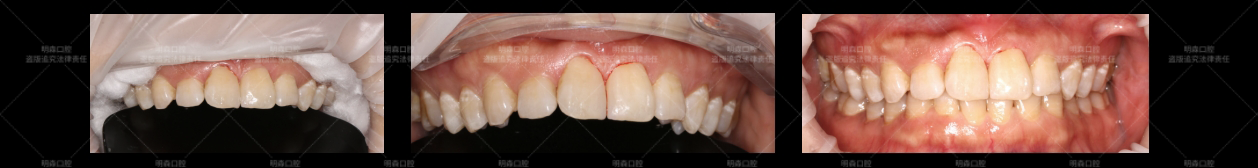

我进行口腔检查时发现,她的11和21 号牙之间宽度足有1-1.5mm,两颗门牙还微微扭转。而且,23 号牙是先天缺失的,好在没有间隙问题,主要困扰还是前牙的“缝隙”。

“之前了解过正畸,说要戴两年牙套,我这工作哪抽得出时间定期复诊啊?”张女士(化名)摇着头说:“不想磨牙,总觉得用自己的牙齿才好”。

听到“不磨牙”(实际是极少量磨除)和“快速见效”,张女士(化名)眼睛都亮了:“就选微创贴面!”

结束那天,张女士对着镜子看了足足五分钟。她惊喜地说:“完全不硌,像自己长出来的一样!”,3个月后我们再次随访发现,贴面完好无损,边缘封闭良好,牙龈健康没问题。

张女士反馈说:“现在开会谈判笑容更自信了,这效果远超预期。”!